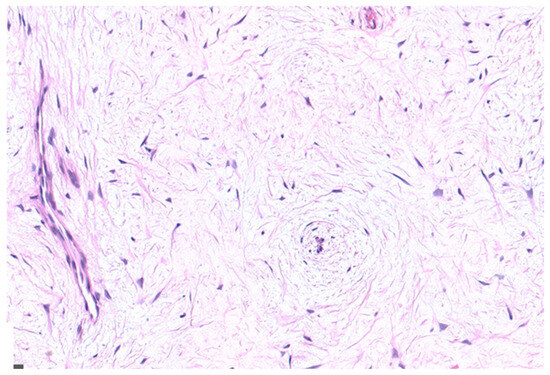

2.1. Case Presentation